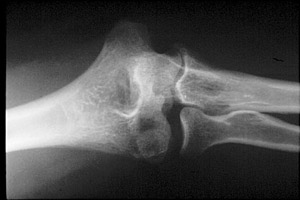

- Click on the image for a larger versionBAP radiograph of the elbow. This shows the fracture of the capitellum.